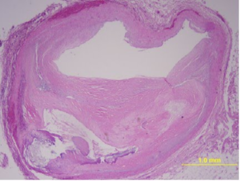

What is shown in the following cross section?

Cross section of atherosclerotic vessel.